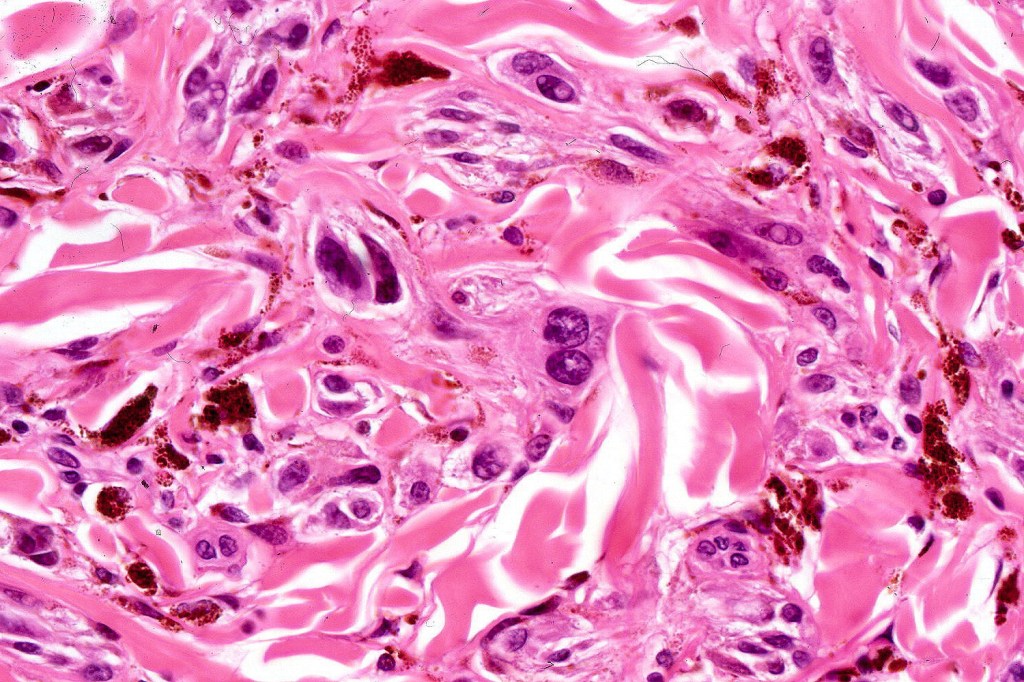

•Admixture of spindle cells, pigmented bipolar or dendritic cells & melanophages

•Cytoplasm is pale and nuclei are small with inconspicuous nucleoli

•An alveolar pattern is characteristic particularly with clear cell nodules

•Mitoses are typically very sparse or absent

•Stromal fibrosis, myxoid change, vascular hyalinization with cyst formation are often seen

•Some tumors are composed spindle cells in a fascicular or neuronevoid pattern